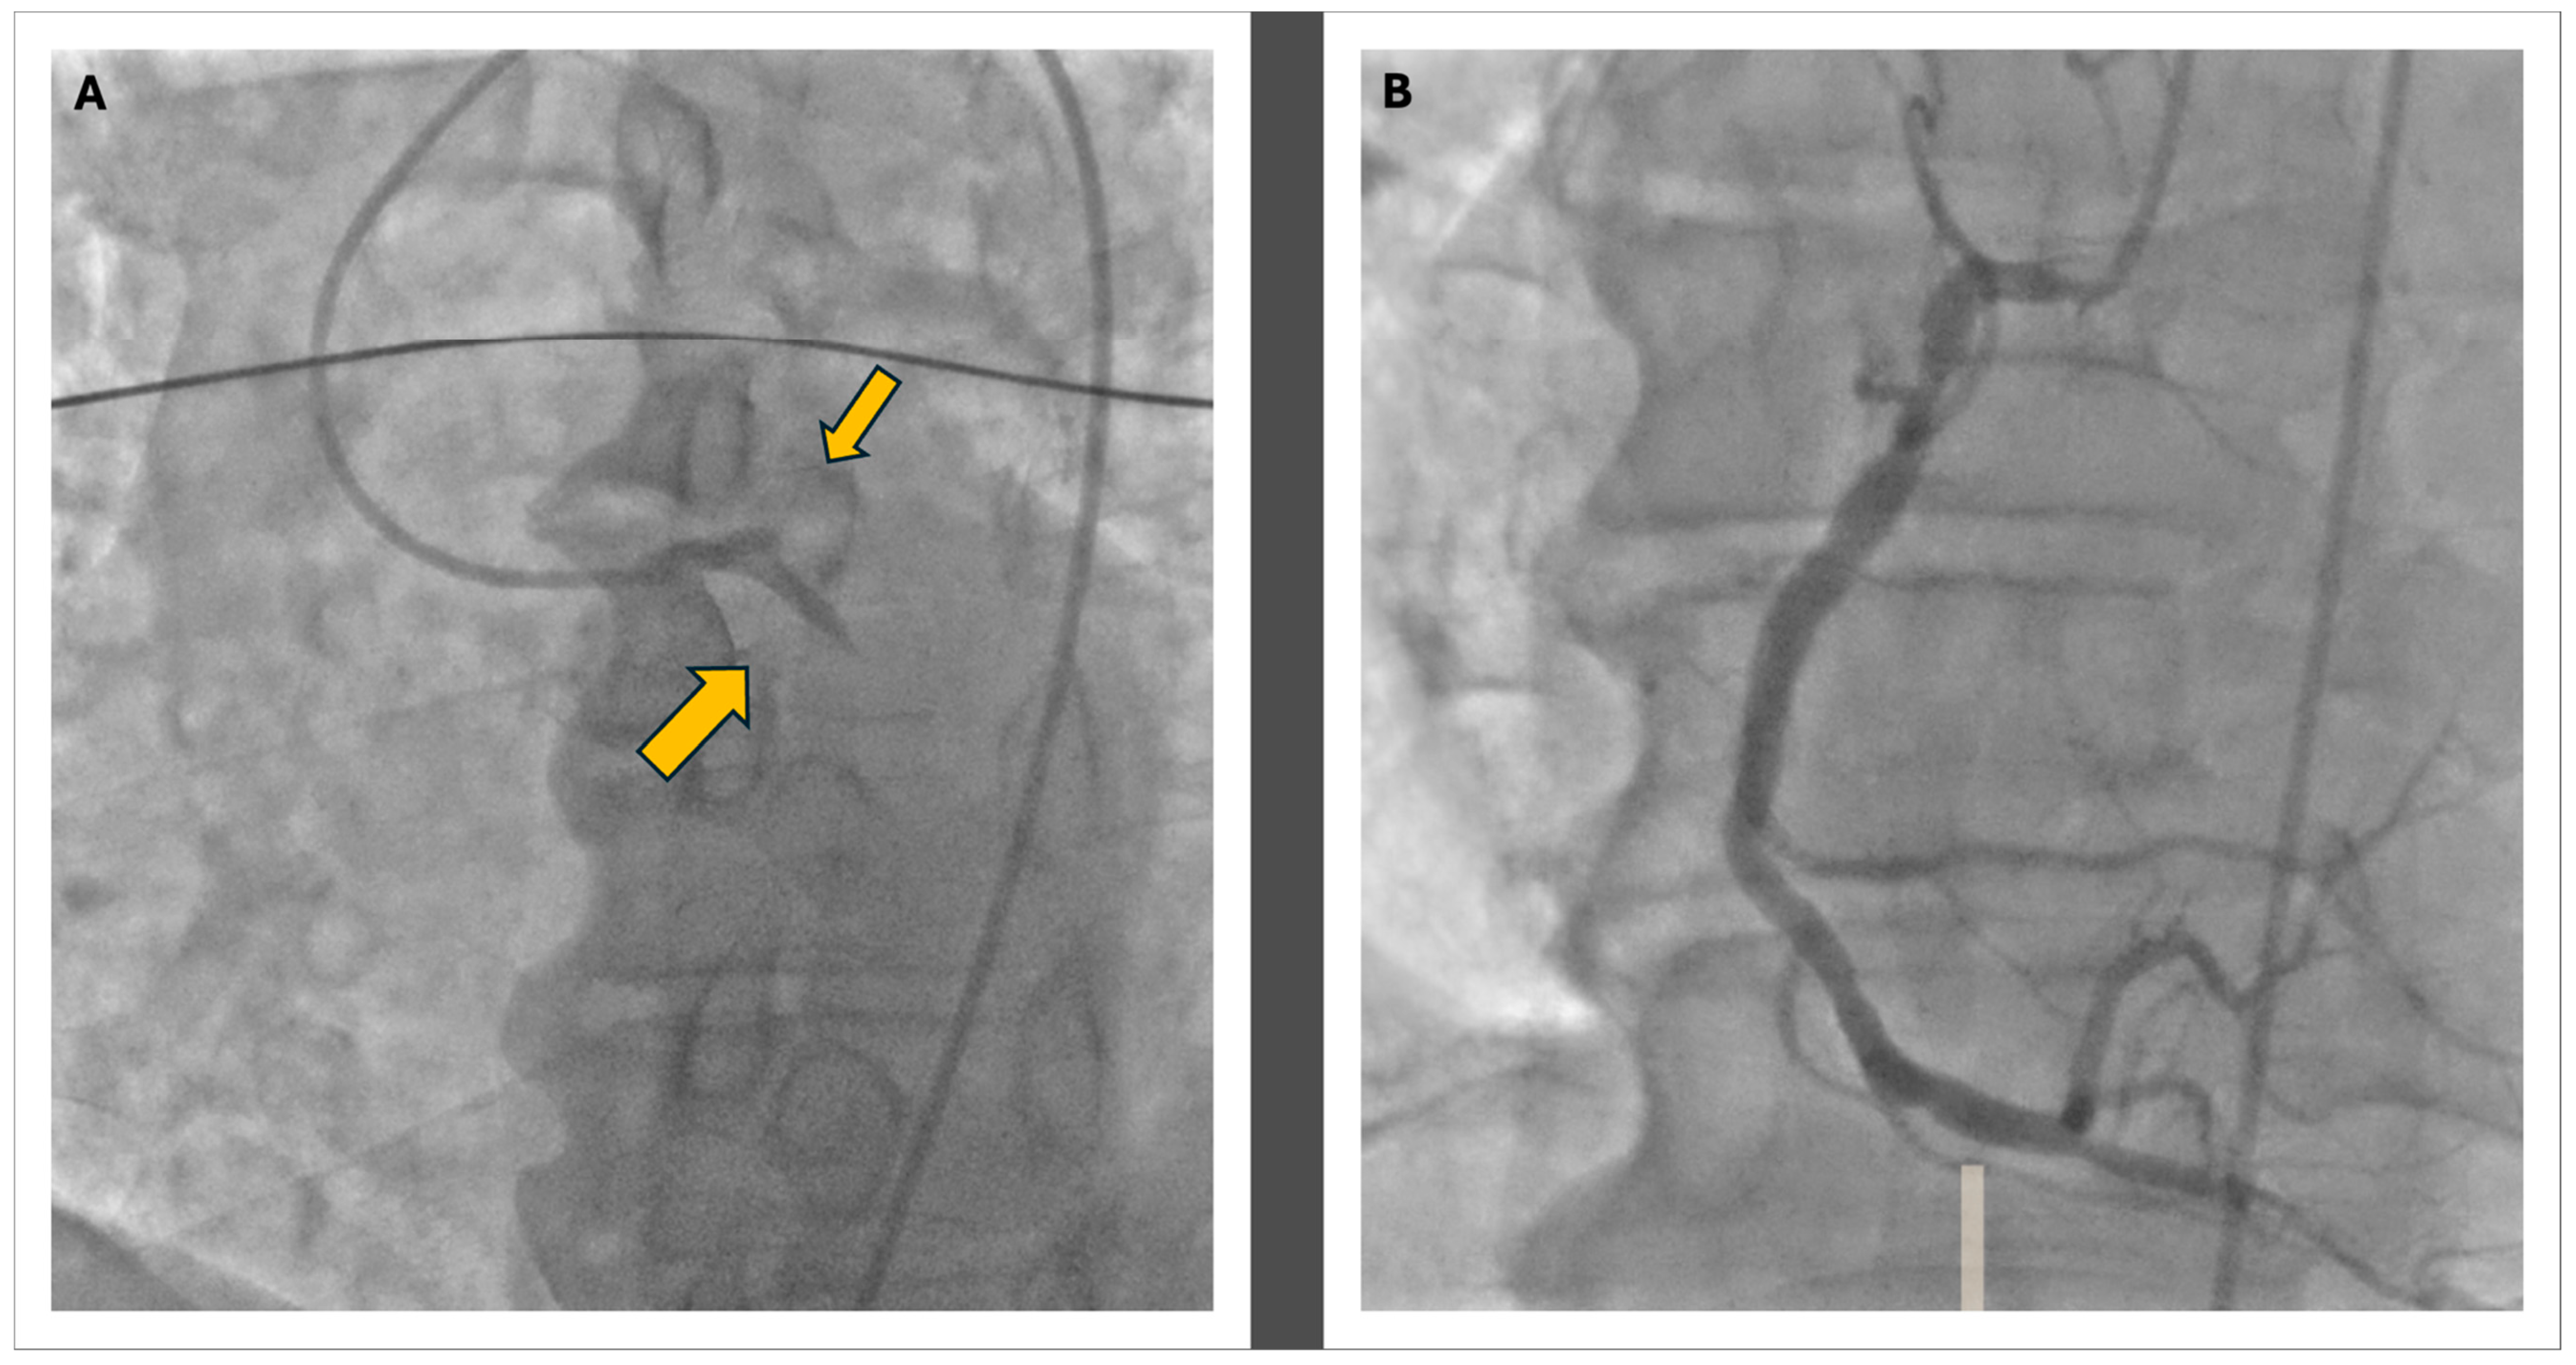

In response to the cardiogenic shock, which led to severe hypotension, inotropic therapy with norepinephrine and dobutamine was initiated. The patient was then transferred to the catheterization lab within 90 min of arrival to the emergency department, where acute subocclusion of the proximal circumflex branch and proximal LAD was identified as shown in Figure 2. Mechanical thrombus aspiration was performed through dual femoral access; the first was to perform angioplasty with greater support and the second was to position the intra-aortic balloon pump (IAPB) to support hemodynamics. Stents were placed in the proximal circumflex branch and proximal LAD. The distal LAD was treated with plain old balloon angioplasty (POBA). After the coronary angioplasty procedure, the patient was placed on dual antiplatelet therapy (DAPT) with acetylsalicylic acid 100 mg daily, following a loading dose of 250 mg IV, and prasugrel 10 mg daily after a loading dose of 60 mg orally.

Figure 2. The coronary angiography: Panel (A) shows the double thrombosis of the left coronary artery at the proximal level of the LAD and the CFX with a TIMI 0 in both vessels, as the indicated by the yellow arrows; in Panel (B), the morphology of the right coronary artery is visible, displaying widespread atheromatous wall changes.